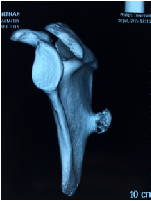

An Unusual Presentation of Osteochondroma on the Dorsal Surface of the Scapula- A Review of Literature

SupreethNekkanti*, SagarSavsani, Malavika Nair, VikramLoona, Trisha Vadapalli, Sagarika Manjunath